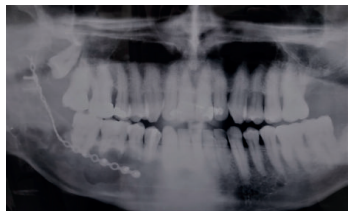

Acudió a servicio de cirugía oral, derivado por su odontólogo, un paciente varón de 65 años sin antecedentes médicos de interés, tras comprobar un importante crecimiento de una imagen radiotransparente respecto a última radiografía de hacía 5 años. El paciente no refirió sintomatología asociada. A la exploración extraoral no se apreció ningún tipo de deformidad ni afectación ganglionar. A la exploración intraoral pese a que se constató la integridad de las corticales, las cuales no estaban abombadas, sí que se pudo apreciar a la palpación un signo positivo de Dupuytren o de “Ping-Pong”. Además se constató una falta de afectación de los dientes del cuarto cuadrante que no presentaban movilidad y tenían una vitalidad positiva (Figura 1). Como complemento a la exploración clínica se solicitó un estudio mediante TAC, donde se apreció la extensión de una lesión radiotransparente que afectaba a rama y cuerpo mandibular derecho. (Figuras 2 y 3).